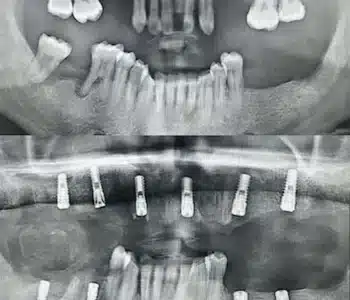

Dr. Seden Aksu is a specialist in modern implantology and surgical dentistry with extensive experience in the management of complex clinical cases. In her practice, she applies comprehensive surgical planning, minimally invasive techniques, and advanced regenerative technologies aimed at restoring both the function of the dentoalveolar system and the aesthetics of the smile. Dr. Aksu has significant experience in performing implant procedures, bone augmentation, and periodontal surgery, including the treatment of patients with severe bone loss. The primary goal of her work is to achieve stable, long-term outcomes in implant rehabilitation and the restoration of oral tissue health.